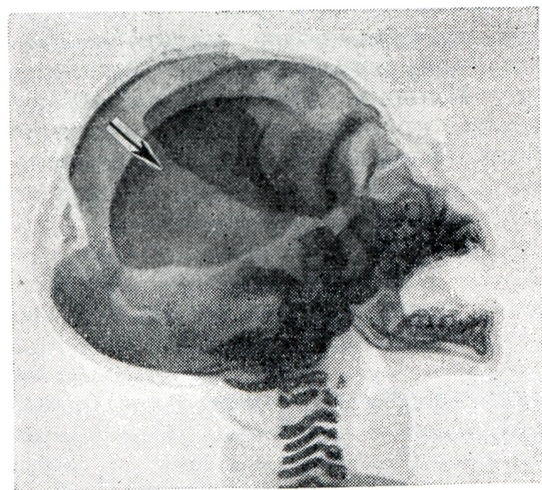

Костный скелет плода при Внутриутробная смерть характеризуется изменившимся по сравнению с нормой положением отдельных частей скелета и неправильными взаимоотношениями костей черепа, позвоночника и конечностей; в костях черепа происходят такие изменения, как черепицеобразное захождение краёв костей друг за друга (рисунок 1), уменьшение вследствие этого размеров черепа, расхождение костей со ступенчатым смещением одной кости по отношению к соседним, деформация черепа (уплощение свода или мешкообразная вытянутость формы).